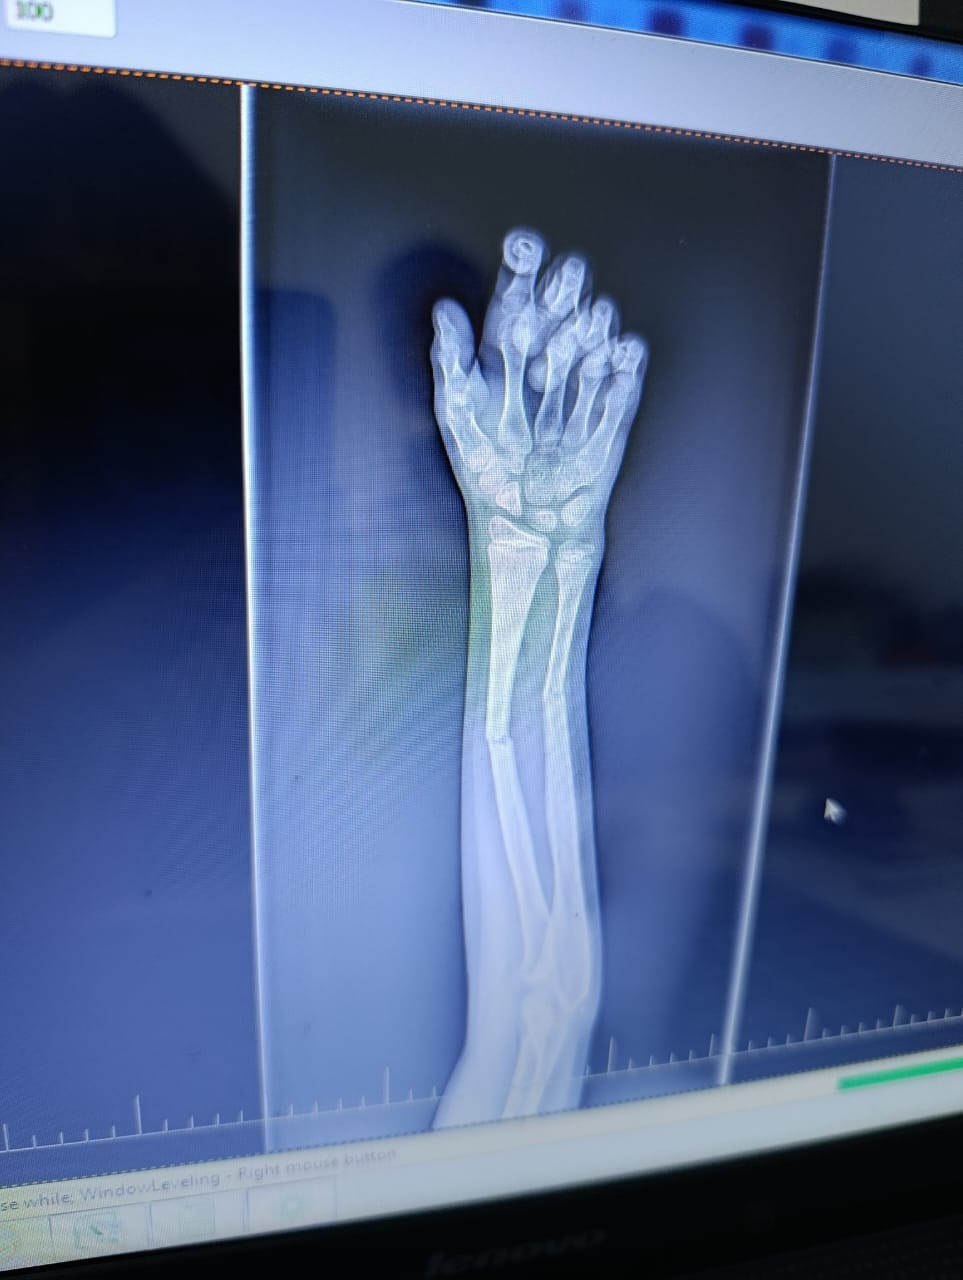

Здравствуйте, у сына, 10 лет, был перелом двух костей на правой руке. Одну кость вправили хорошо, другую на 50%. Врач говорит, что нет необходимости довправлять другую кость, но я переживаю и не понимаю как она может срастись. Сперва неделю ходил с лангетой, потом поставили гипс. Посмотрите пожалуйста снимки. Может ли кость нормально сростись или нужно настоять на операции, что бы вторую кость установили более ровно?